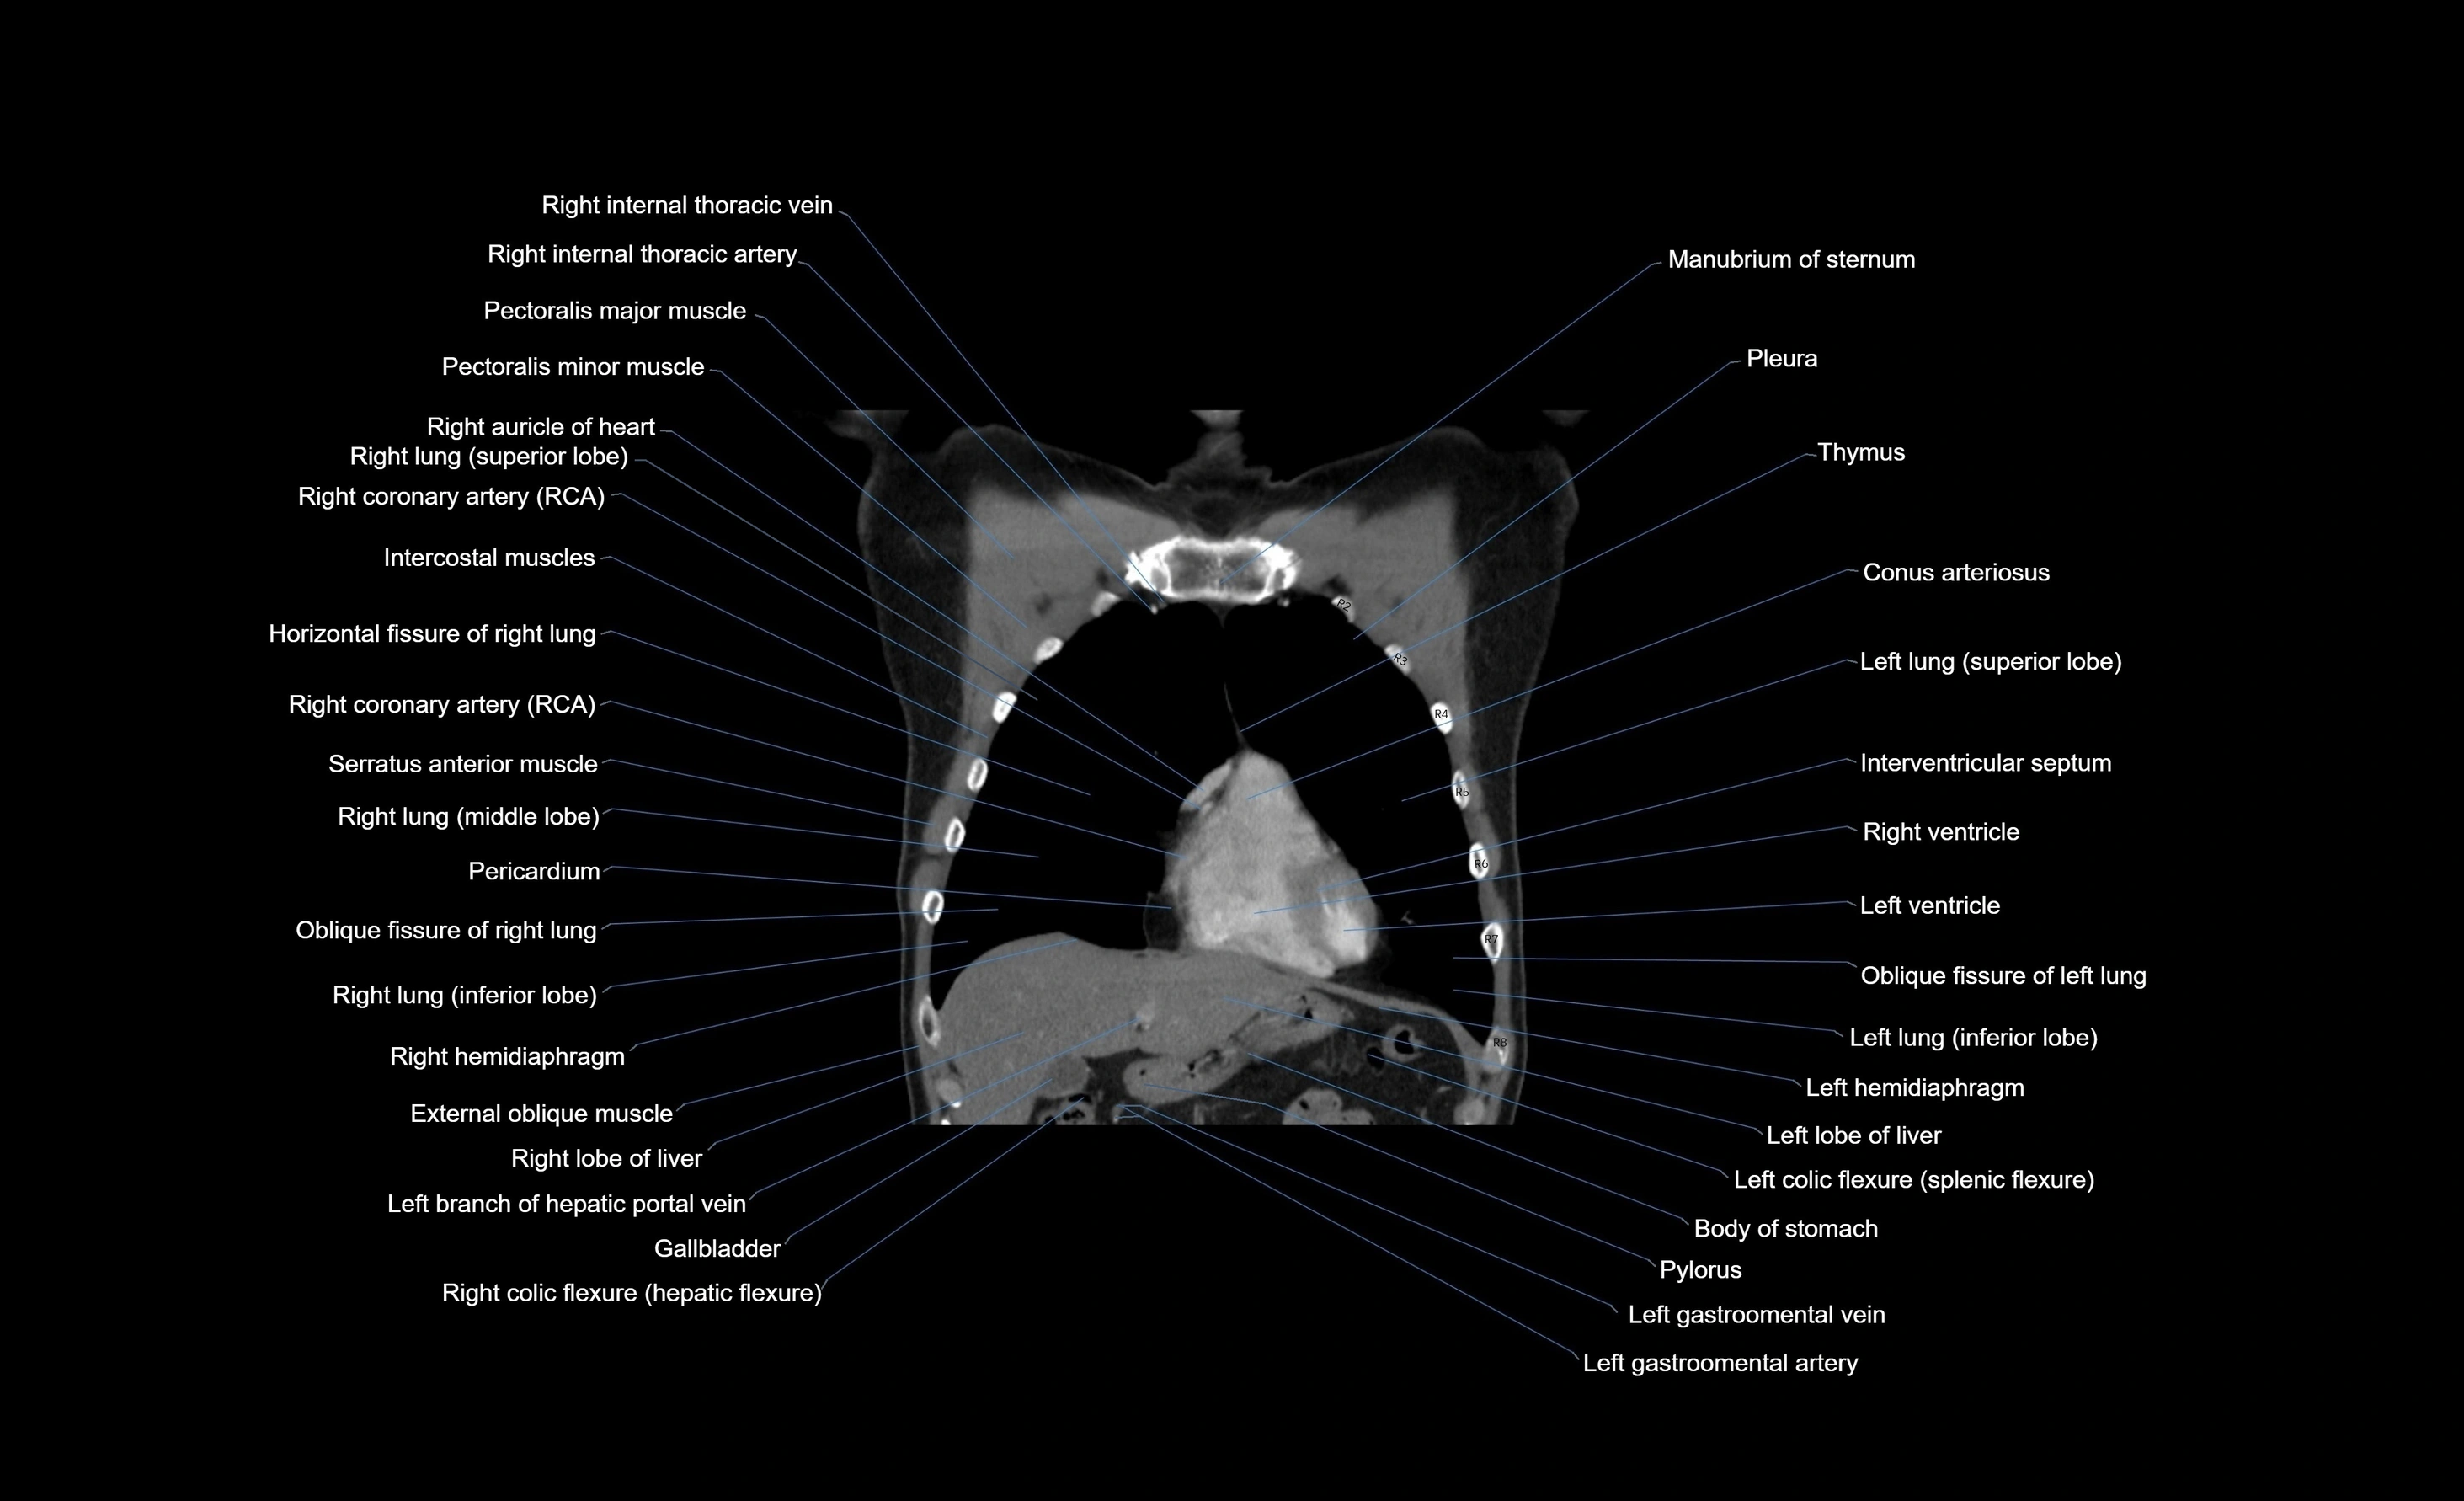

- Conus arteriosus

- External oblique muscle

- Gallbladder

- Horizontal fissure of right lung

- Inferior vena cava

- Internal thoracic artery

- Internal thoracic veins

- Interventricular Septum

- Left hemidiaphragm

- Left lobe of liver

- Left lung (inferior lobe)

- Left ventricle

- Manubrium of sternum

- Oblique fissure of left lung

- Oblique fissure of right lung

- Pectoralis major muscle

- Pectoralis minor muscle

- Pericardium

- Pleura

- Right auricle of heart

- Right coronary artery (RCA)

- Right hemidiaphragm

- Right internal thoracic artery

- Right internal thoracic veins

- Right lobe of liver

- Right lung (inferior lobe)

- Right lung (middle lobe)

- Right lung (superior lobe)

- Right ventricle

- Serratus anterior muscle